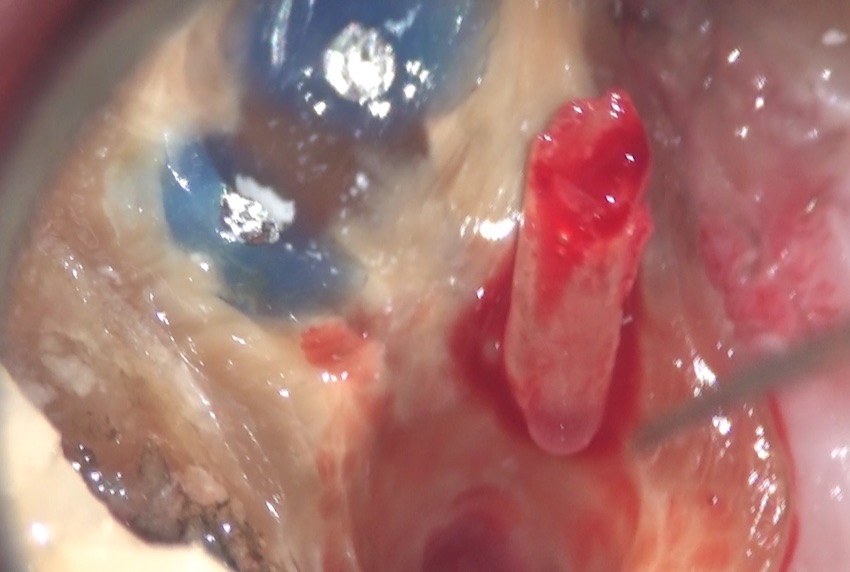

内部からは、ニキビを潰した時に出てくるような、体液が出てきています。

特殊なバキュームでその体液を吸引すると、

大きな穴ぼこが空いていました。

赤い→で示したのがそうです。

術前のCT画像からも分かっていたのですが、この大きな穴の中には、前医の入れてしまったファイバーポストのカケラが落ちているのが分かっていましたので、特殊な器具で内部を探ると、

内部からカケラが出てきました。取り出せて良かったです。